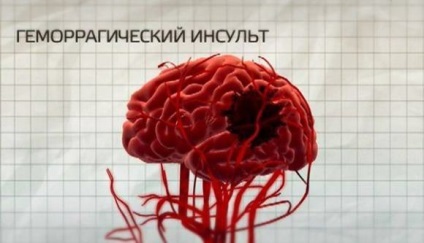

hemoragică

accident vascular cerebral hemoragic apare atunci când o ruptură vas și sângerare la nivelul creierului

accidente vasculare cerebrale hemoragice sunt caracterizate prin prezența hemoragiei cerebrale. Ei vin în mai multe forme, precum și ischemică. Efectele lor tind să fie mai grave, multe dintre schimbările care au loc după hemoragiei, ireversibil. Acest lucru se datorează faptului că este dificil de a opri sângerarea destul în interiorul capului, iar un hematom afecteaza celulele creierului sensibile și neprotejate ca o lovitură. Mortalitatea din această formă de accident vascular cerebral atinge cele mai mari note (aproximativ 40-70%).

Principalul motiv pentru acest tip de accident vascular cerebral - hipertensiune arterială.

Presiunea crescută în vasele de atenuare pereții lor crește permeabilitatea lor. În plus, în timpul unei crize hipertensive a generat un spasm al arterelor cerebrale constant. Toate acestea sunt însoțite de modificări ale metabolismului celular, prin pereții vaselor devin permeabile la plasma sanguină. De multe ori există focare multiple, ceea ce reduce probabilitatea unui rezultat de succes.

accident vascular cerebral hemoragic este în curs de dezvoltare foarte rapid, dintr-o dată, fără nici un simptom anterioare. Pacientul prezintă dureri de „greva“ (dacă este comoție), simptome acute. Tratamentul trebuie să fie redat imediat, în caz contrar sângerare va deveni atât de mare încât pacientul nu poate fi salvat.